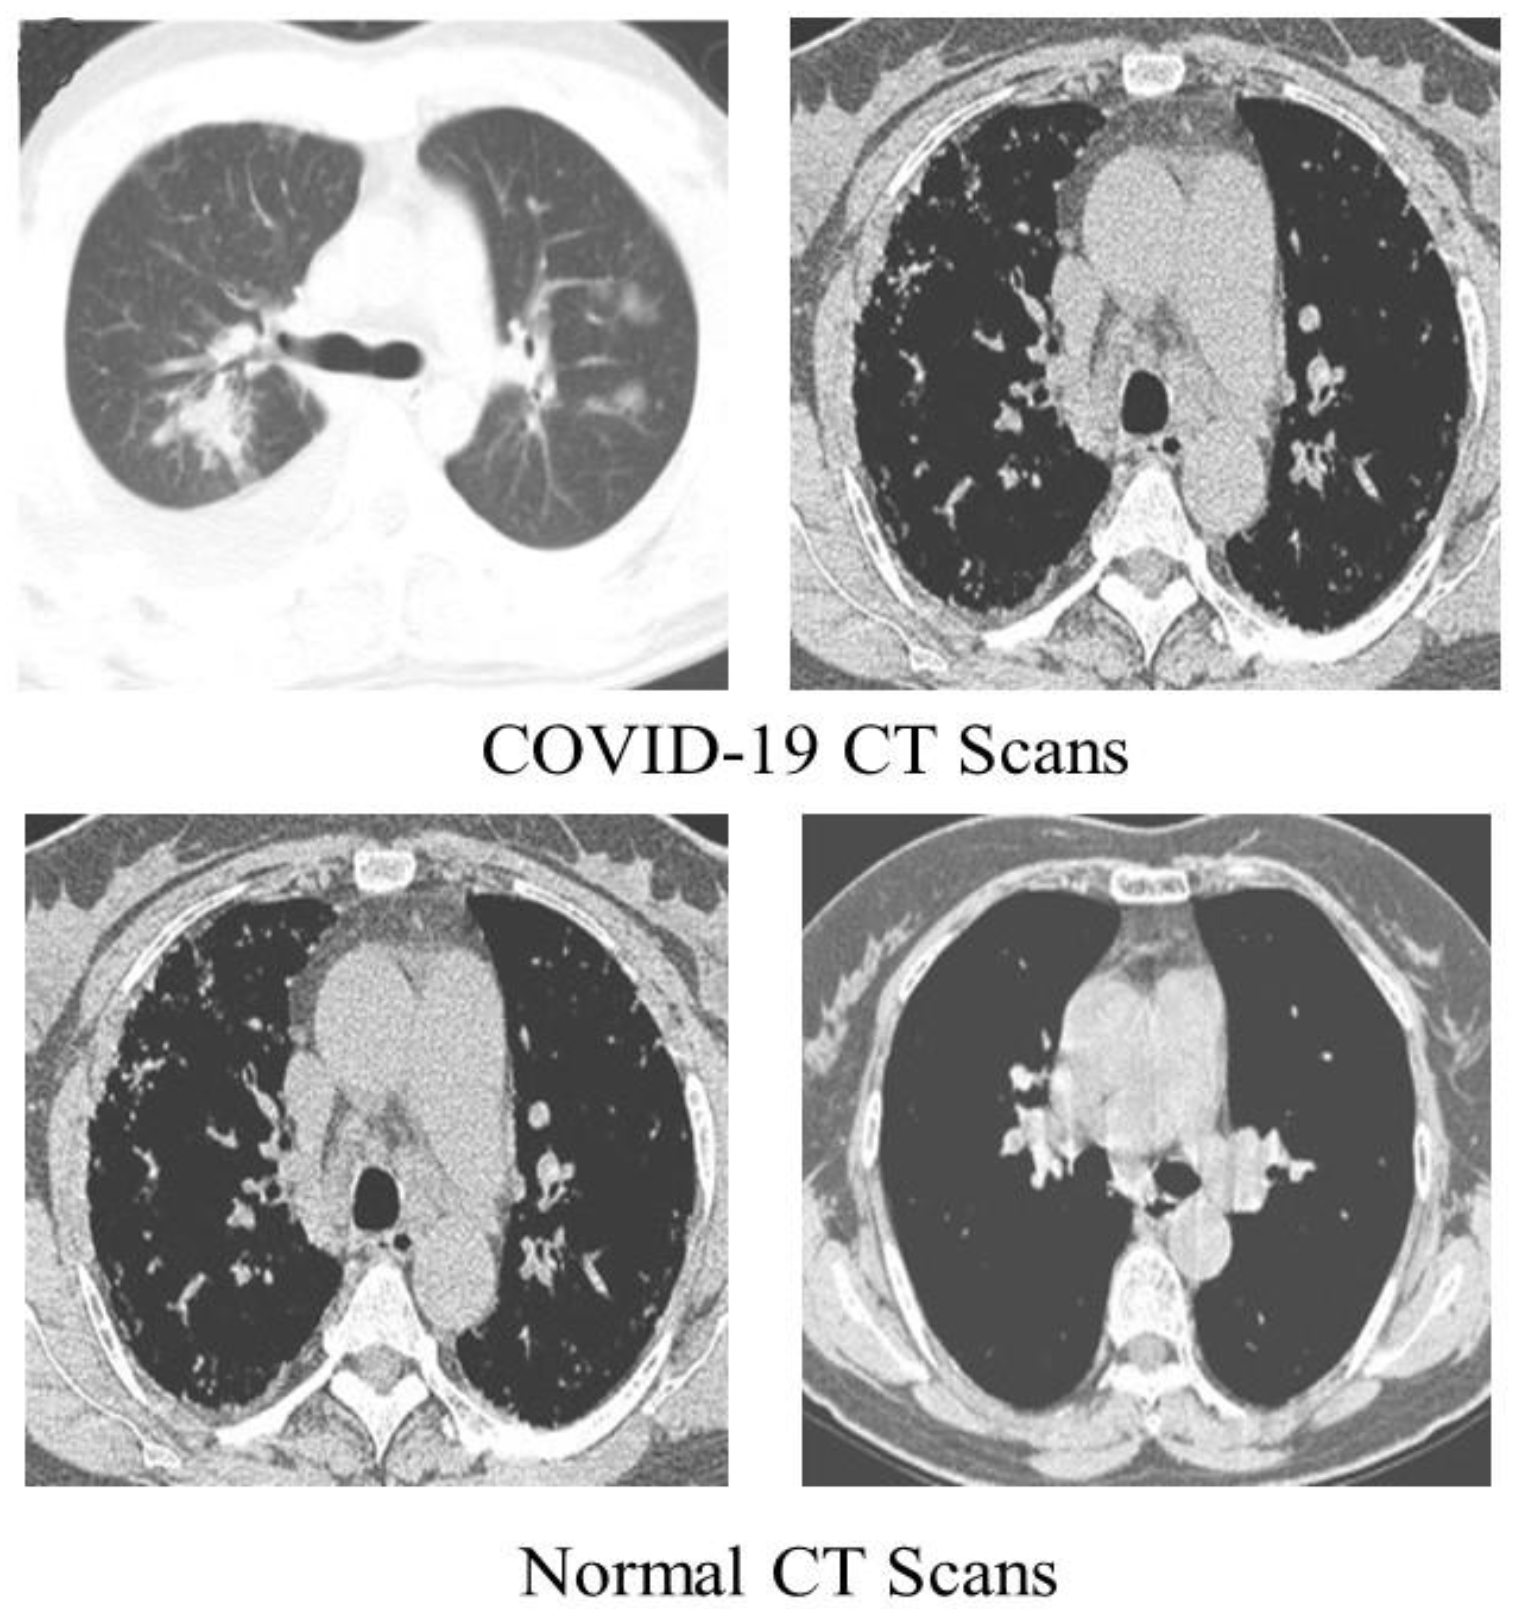

We detected COVID-19 by utilizing CT scans from a freely accessible SARS-CoV-2 CT scan dataset [44] comprising 1252 CT scans of COVID-19 patients, with 1230 CT scans of normal people (total of 2482 CT scans). These statistics were gathered from real patients in Brazilian hospitals. Figure 4 displays a few examples from the dataset.